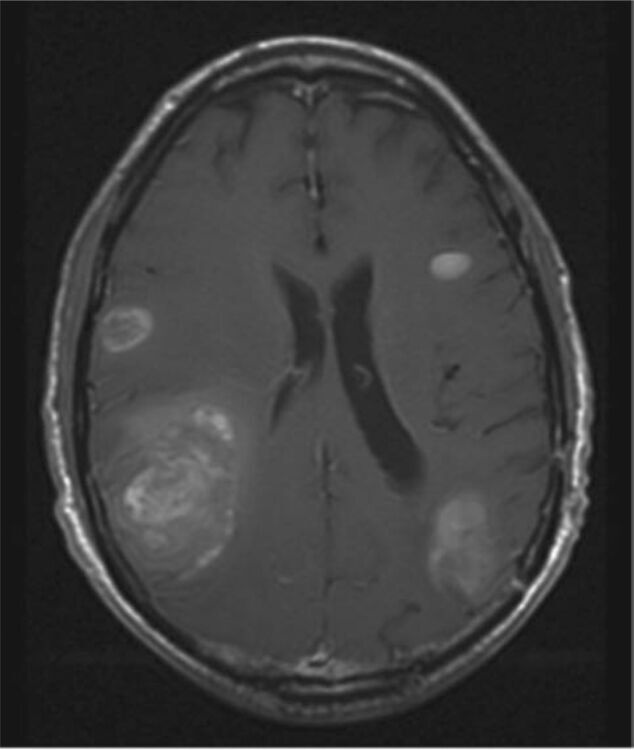

Join us every Thursday at 8:30 a.m. for a unique and informative Zoom event where medical experts gather to conduct a Brain Metastasis Tumor Board. During this virtual gathering, doctors will meticulously review complex patient cases, sharing their insights and knowledge on the latest advancements in brain metastasis treatment.

This interactive event is a valuable opportunity to witness the collaboration of top multi-disciplinary medical professionals as they discuss challenging cases and explore innovative solutions. To participate, registration for the event is required. Don't miss out on this weekly insight into the world of brain metastasis treatment and research!